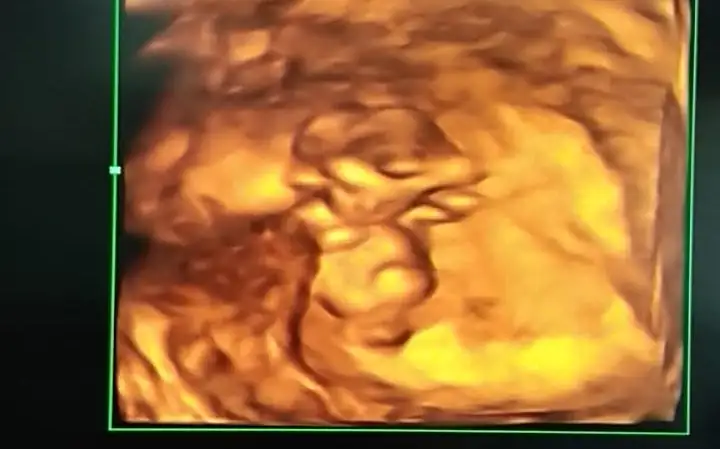

Hem net değil hemde 11 12 13 hafta olmalıBana da tahmin yapabilir misiniz 15+1 göstermedi cinsiyeti bugün bıcırık :)Ikra meyra

Mrb 13 haftalik olduk cok sukurKız gibi net de değil kız sanki 12-13 olunca tekrar usg paylaşın

Kız gibiMrb 13 haftalik olduk cok sukur

Kız gibi

bu da diger acidan fotografi ayagi kapatmis gibi amabu bu haftaki goruntusu 12. hafta gecen hafta erkek demistiniz ama emin olamamistiniz@ikrameyra